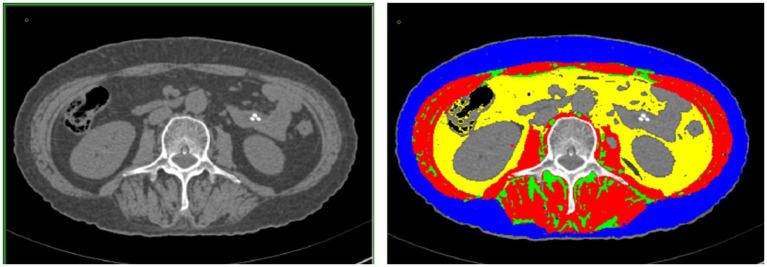

METHODS

We conducted a retrospective analysis to collect the clinical data of patients with GC who underwent surgery after receiving NAC at the First Hospital of Lanzhou University from January 2016 to December 2022. Based on the presence of a post-NAC downstaging period and postoperative complications, we categorized the patients into group A (downstaging without complications), group B (downstaging with complications), group C (non-downstaging with complications), and group D (non-downstaging without complications). First, we assessed the OS disparity between the groups. Subsequently, we performed a comparative analysis of the body composition and hematological indexes of patients from the four groups.

We included 295 patients in the study and categorized them into four subgroups: group A comprised 83 patients (28.1%), group B comprised 32 patients (10.8%), group C comprised 83 patients (28.1%), and group D comprised 97 patients (32.9%). Group A patients had the longest OS of 40.1 ± 20.53, whereas group C patients had the shortest OS of 32.15 ± 25.09. The OS of patients in the other two groups was between these values. Pairwise comparisons revealed significant differences between the OS of group A patients and that of groups C (32.15 ± 25.09) and D (33.06 ± 20.89) patients ( < 0.05). The skeletal mass index (SMI) and skeletal mass area (SMA) were highest in group A, lowest in group C, higher in group A (SMI: 45.05 ± 7.44, SMA: 128.88 ± 22.67) than in group C (SMI: 41.61 ± 8.17, SMA: 115.56 ± 26.67) ( < 0.05), and higher in group D (SMI: 44.94 ± 6.87, SMA: 127.05 ± 23.09) than in group C ( < 0.05). However, we observed no significant difference between the SMI and SMA of groups B (SMI: 42.91 ± 9.68, SMA: 120.76 ± 30.51) and D ( > 0.05). With respect to hematological indexes, the prognostic nutritional index (PNI) was highest in group A and lowest in group C. The PNI in group A (417.89 ± 37.58) was significantly higher than that in group C (397.62 ± 47.56) ( < 0.05), and it was also higher in group D (410.76 ± 4.28) than in group C ( < 0.05). However, we observed no significant difference between the PNI in groups B (402.57 ± 53.14) and D ( > 0.05).

Patients with advanced GC who experienced post-NAC downstaging and no postoperative complication had the longest OS. Patients with better body composition demonstrated more significant downstaging, fewer postoperative complications, and a longer OS.